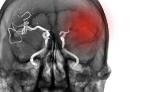

뇌혈관질환 전조증상 9가지

한 번쯤 들어본 말일 거예요. 뇌출혈, 뇌경색 같은 뇌혈관질환은 ‘예고 없이 찾아오는 병’이라고. 그런데 막상 당하는 사람들 대부분은요, 꼭 그렇지만은 않다고 말해요.

이런 얘기, 뉴스에서 자주 듣죠. 그래서 오늘은요, 겉으로 드러나지 않지만 뇌혈관에 이상이 생기기 시작했다는 ‘신호’를 우리 몸이 어떻게 보내는지를 9가지로 정리해볼게요.